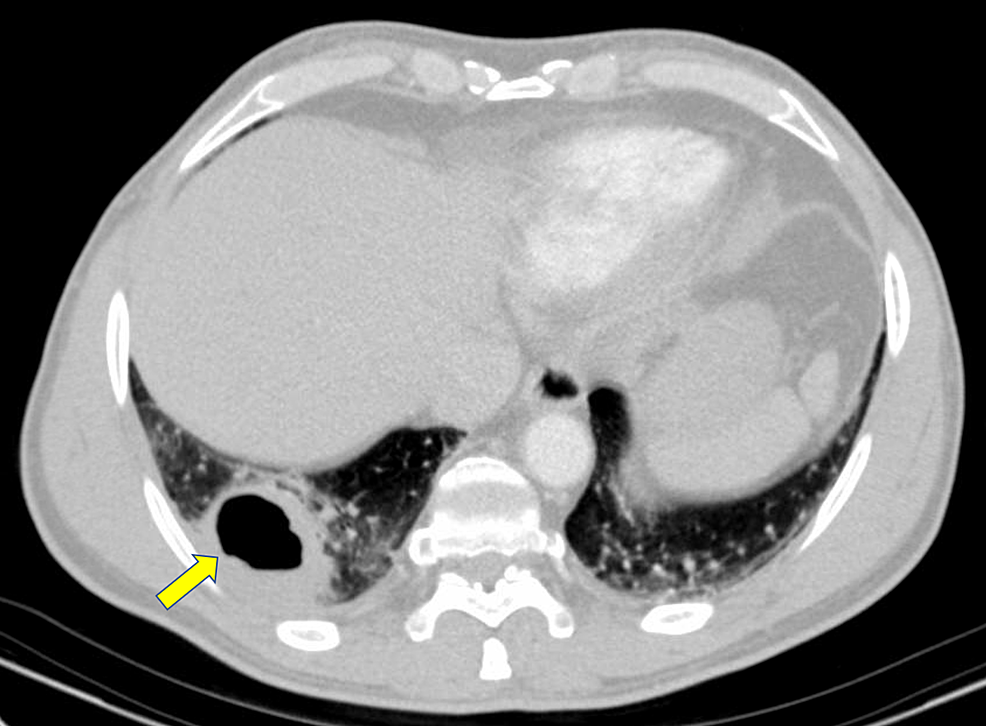

What Is A Cavitary Lung Mass . a lung mass with a central area of nonenhancing lung (red arrow) is surrounded by a rim of enhancement (yellow arrow), suggesting. the wall thickness of the cavitary lung lesions in solitary disease. cavitary lung lesions are relatively common findings on chest imaging and often pose a diagnostic challenge to the hospitalist. a cavitary lung lesion is defined radiographically as a lucent area contained within a consolidation, mass, or nodule. a pulmonary cavity is a collection of gas and/or fluid enclosed by a thick and often irregular wall which usually occurs when central necrotic tissue is.

the wall thickness of the cavitary lung lesions in solitary disease. a cavitary lung lesion is defined radiographically as a lucent area contained within a consolidation, mass, or nodule. cavitary lung lesions are relatively common findings on chest imaging and often pose a diagnostic challenge to the hospitalist. a pulmonary cavity is a collection of gas and/or fluid enclosed by a thick and often irregular wall which usually occurs when central necrotic tissue is. a lung mass with a central area of nonenhancing lung (red arrow) is surrounded by a rim of enhancement (yellow arrow), suggesting.